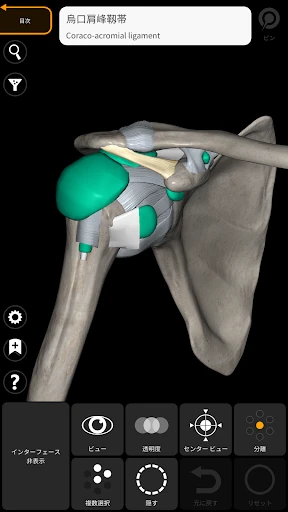

3Dアトラスの驚きの体験

皆さん、3Dで人体を探検したことはありますか?このアプリを使うと、まるで本物の標本を手に取っているかのように、人体の構造を詳細に観察できます。何よりも嬉しいのは、非常にリアルなグラフィックスです。3Dモデルはとても精密で、筋肉や骨、内臓の位置関係が一目瞭然です。

この「解剖学 - 3Dアトラス」、ただのビジュアルツールにとどまりません。かなり多くの情報が詰まっています。例えば、各部位の詳細な説明や、医学用語の解説も充実しているので、学習にはもってこいです。特に、試験勉強中の学生さんには非常に役立つことでしょう。

私のお気に入りの機能の一つは、特定の部位を選択すると、その部位に関する詳細な情報が表示されることです。これにより、単なるビジュアルだけでなく、知識を深めることができるのです。